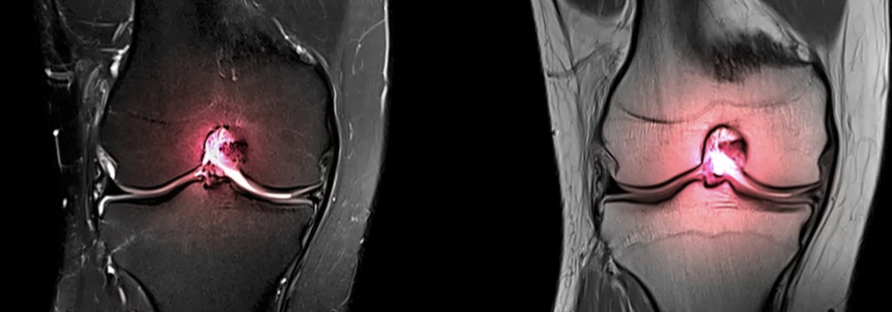

십자인대 파열은 무릎 관절의 안정성을 담당하는 중요한 인대 중 하나인 전방 십자 인대(ACL)가 손상되는 부상입니다. 이러한 부상은 스포츠 활동 중에 흔히 발생하며, 갑작스러운 방향 전환, 정지, 또는 점프로부터 착지하는 동작에서 주로 발생합니다. 십자인대 파열의 주요 증상으로는 부상 당시 무릎에서 '팝'하는 소리가 들리는 것, 심한 통증, 부기, 무릎의 불안정성 및 움직임 범위의 감소가 있습니다. 특히, 무릎에 체중을 싣거나 걸을 때 통증이 심해지는 것이 특징입니다. 십자인대 파열은 MRI와 같은 영상 진단을 통해 확인할 수 있으며, 치료 방법은 부상의 정도와 환자의 활동 수준에 따라 보존적 치료 또는 수술적 치료가 고려될 수 있습니다. 십자인대 파열은 적절한 치료와 재활을 통해 회복이 가능하지만, 전문적인 의료진의 진단과 치료 계획이 필요한 중대한 부상입니다.

진단은 일반적으로 환자의 증상과 의사의 신체 검사를 통해 이루어집니다. 필요한 경우, MRI와 같은 영상 진단을 통해 인대의 손상 정도를 더 정확히 평가할 수 있습니다. 치료는 손상의 정도에 따라 다르며, 경미한 염좌의 경우에는 휴식, 얼음 찜질, 압박 붕대, 그리고 무릎을 높이는 것이 도움이 됩니다. 더 심각한 손상의 경우에는 물리 치료, 보조기 착용, 혹은 수술이 필요할 수 있습니다.

1. MRI에서 십자인대 손상이 확인되어야 합니다.